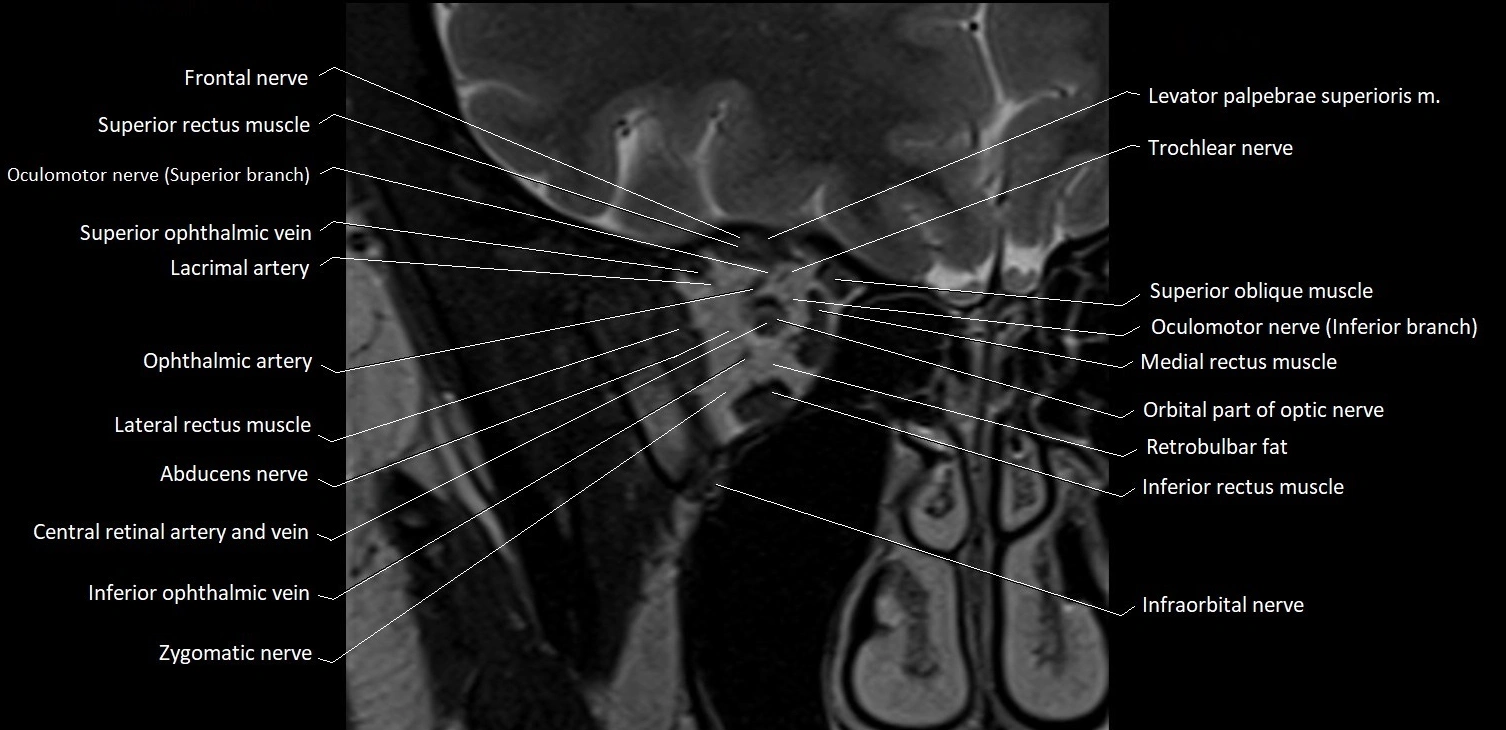

MRI Appearance

The abducens nerve is a small, thin, linear structure

Best visualized on high-resolution T2-weighted 3D MRI sequences (e.g., FIESTA or CISS)

Seen as a hypointense (dark) line running from the brainstem at the pontomedullary junction, traversing the prepontine cistern, and entering Dorello’s canal under the petrosphenoidal ligament, then into the cavernous sinus, and finally the orbit

May be challenging to visualize in standard MRI due to its small size

Pathology may be inferred by absence, displacement, or enhancement of the nerve

MRI images